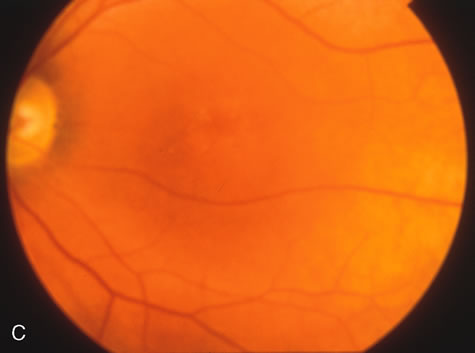

In Stargardt's disease, thes most common hereditary macular dystrophy, FA has a variety of functions. In the mildest fundus presentation, with visual symptoms and visual function out of proportion to the observed maculopathy, FA can confirm or even make the diagnosis and can avoid a mistaken diagnosis of malingering, hysteria, or central nervous system disease (Fig. 9A and B). When a maculopathy is present without surrounding parafoval flecks, FA may show patchy areas of transmission hyperfluorescence in the posterior pole, indicating a more diffuse involvement (Fig. 9C and D).

Fig. 9. Stargardt's disease–fundus flavimaculatus. The mild maculopathy (without parafoveal flecks) (A) is confirmed by the angiogram (B). The relative absence of the underlying choroidal flush, resulting in an easier visualization of the overlying retinal capillary circulation, has been referred to as the “silent” or “dark” choroid, and is considered a common finding in this disease. The diagnosis is confirmed in an individual with a pigmentary maculopathy without flecks (C). Here the angiogram demonstrates widespread transmission hyperfluorescence and a “silent” or “dark” peripapillary area (D). When the posterior pole shows multiple yellowish-white flecks (E), the angiographic findings do not necessarily correspond to the flecks (F). It should also be noted that despite the widespread abnormalities, the background choroidal fluorescence is normal.

In a large majority of patients (86% in one study),20 there is an absence or decrease in the background choroidal fluorescence (which is referred to as the “silent” or “dark” choroid) (see Fig. 9B). This warrants special attention because it occurs so frequently, is rarely found in other retinal disorders,21 and may be related to histopathology that shows an increase in lipofuscin in the RPE.22